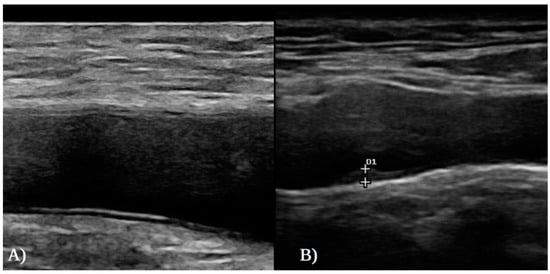

2.4. Ultrasound Study